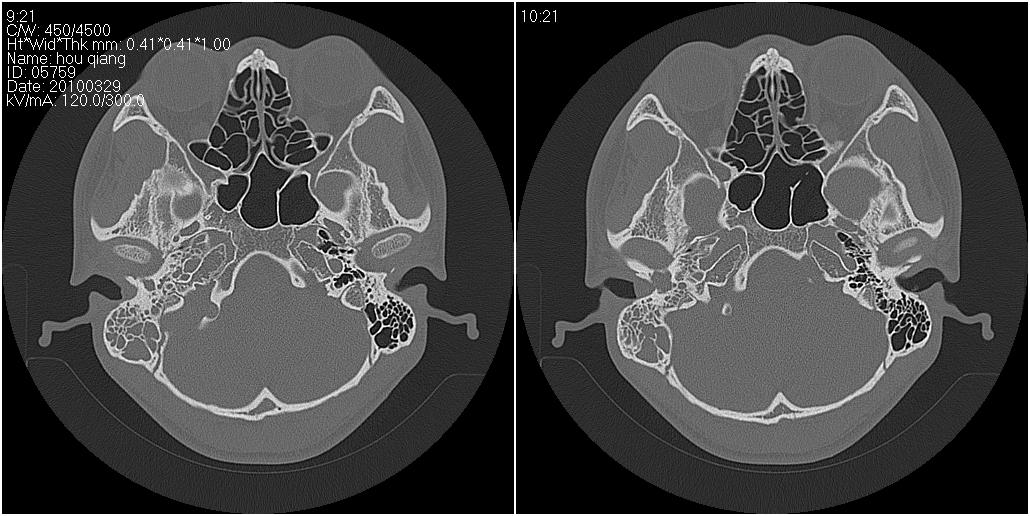

标题: CT25419:男性,18岁。右耳肿、痛5个多月。 [打印本页]

标题: CT25419:男性,18岁。右耳肿、痛5个多月。

1)右侧慢性中耳乳突炎并右侧中耳腔及外耳道肉芽肿或胆脂瘤形成。2)鼻咽腺样体肥大。

右侧中耳乳突炎累及外耳道,鼻咽腺样体肥大。